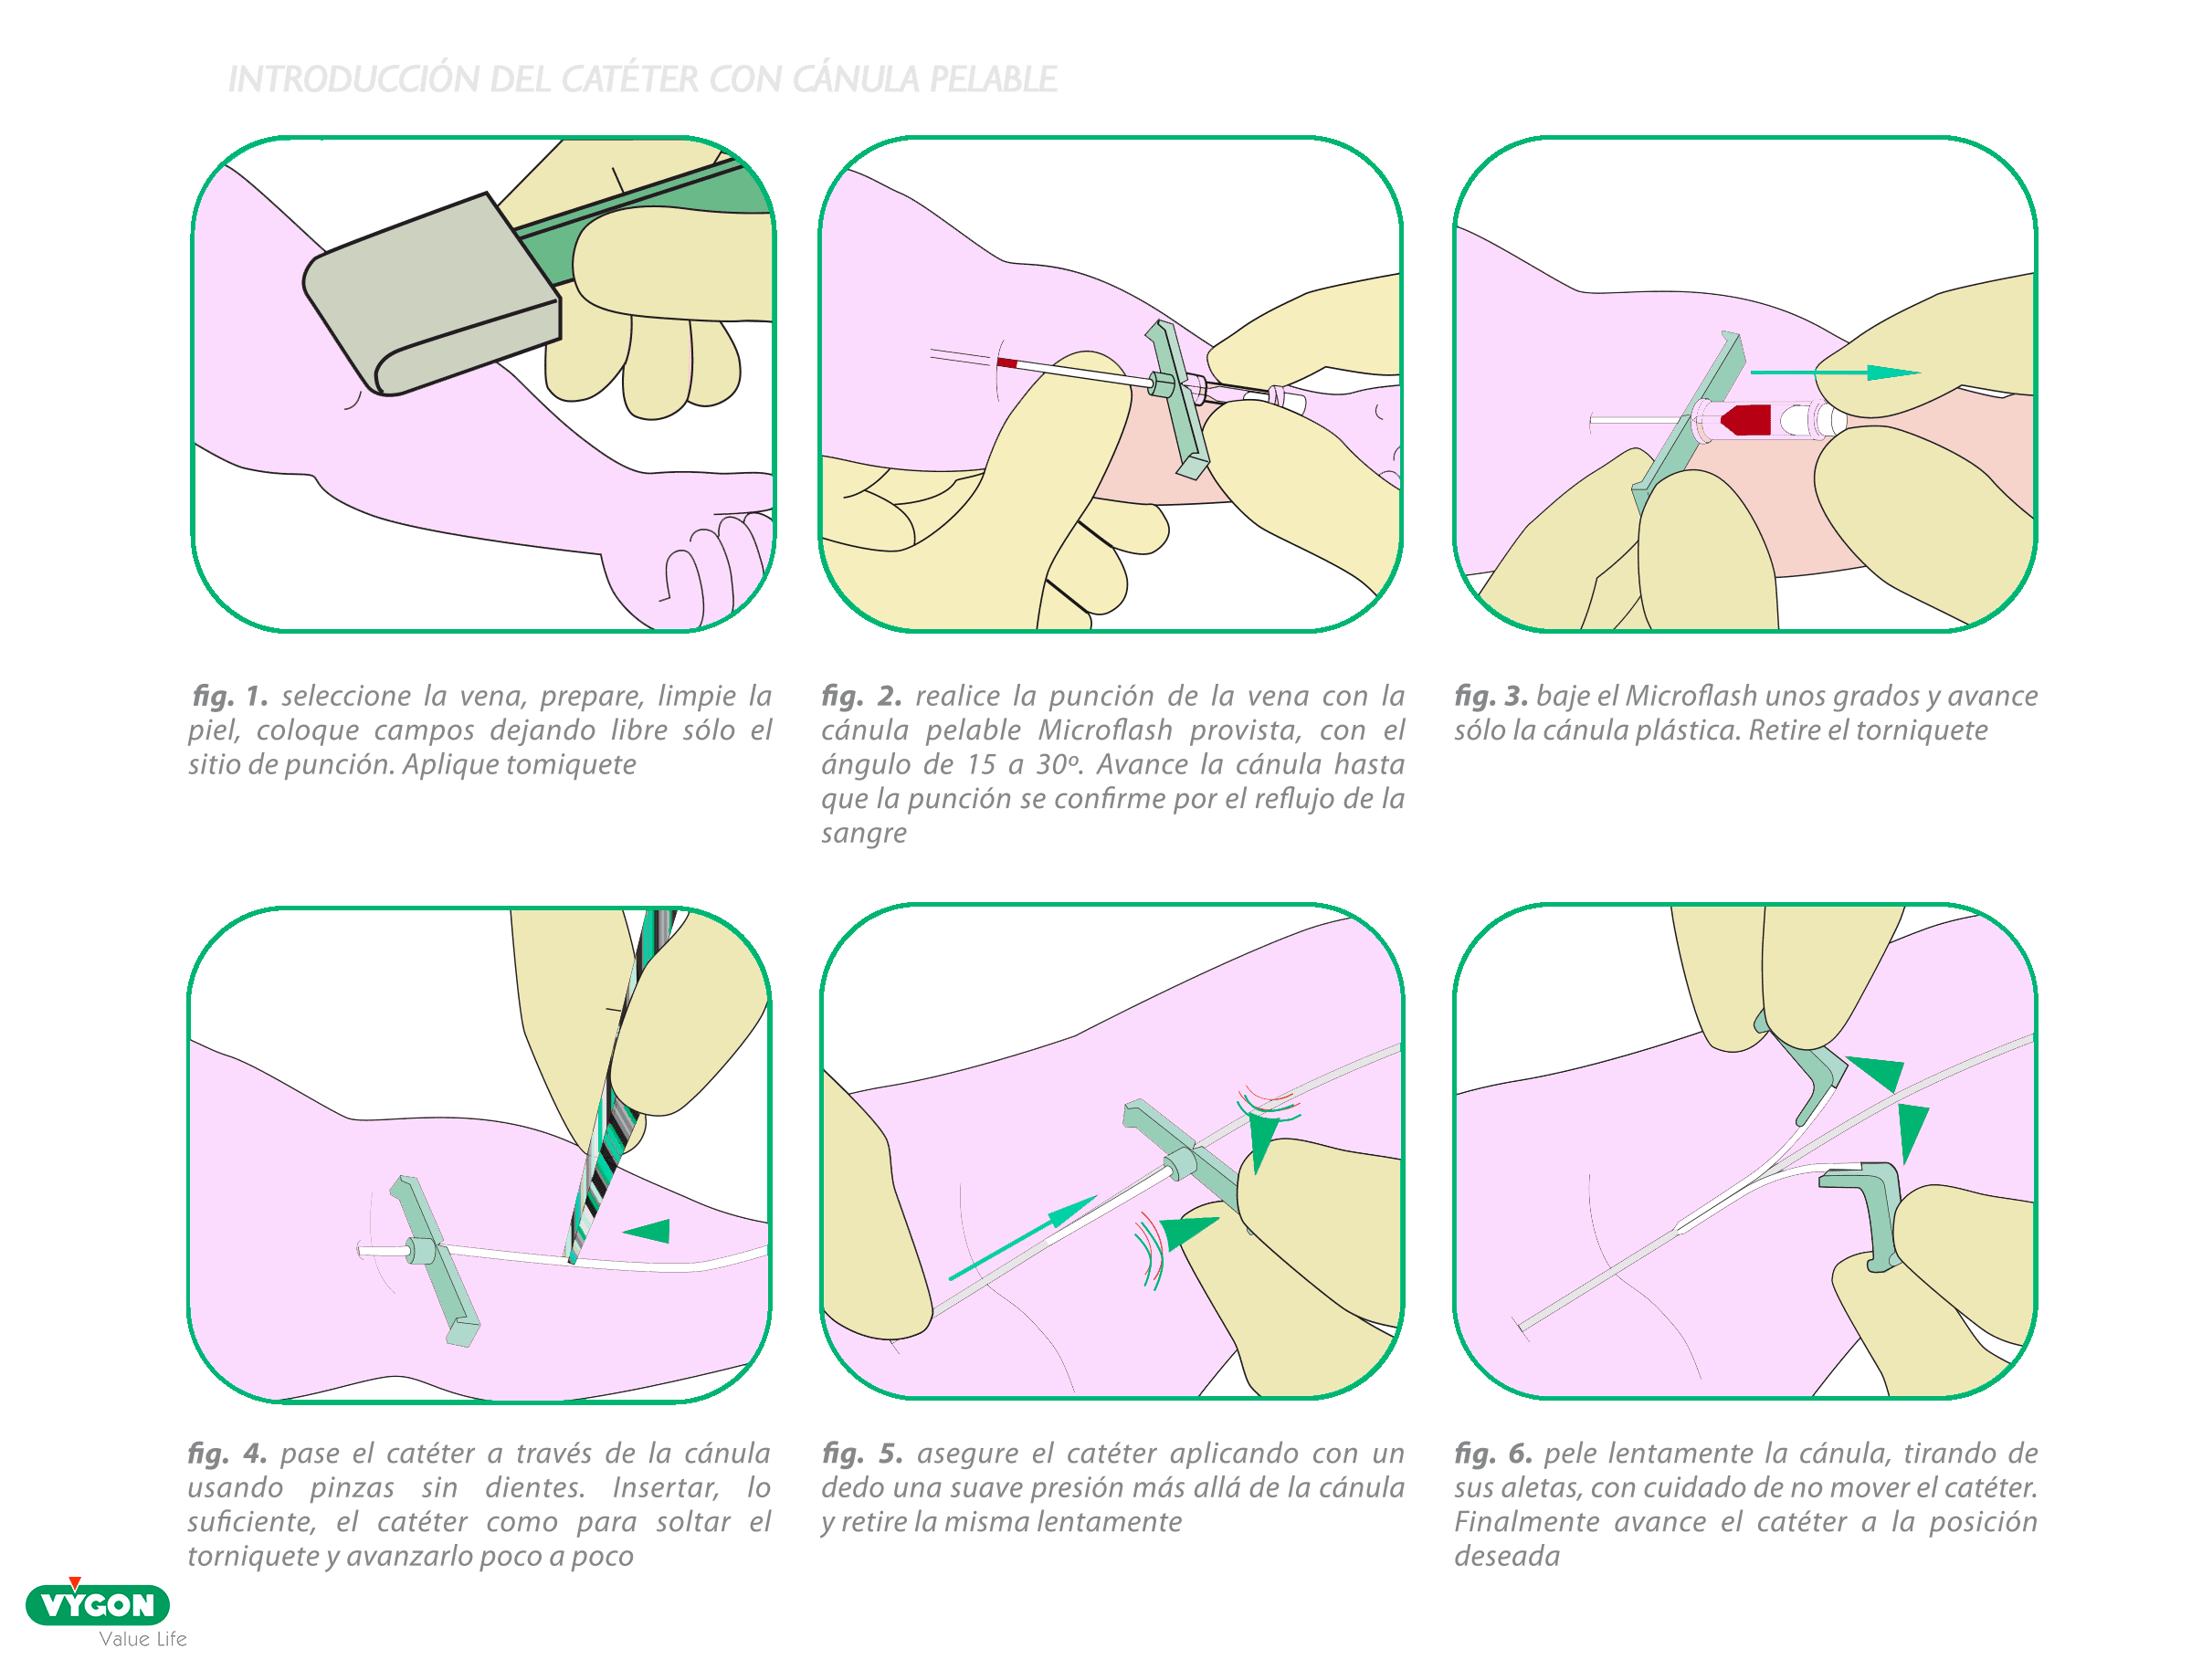

Se trata de un introductor rompible caracterizado por estar compuesto de un catéter corto o cánula y de una aguja interna (como los catéteres cortos periféricos).

VENTAJAS

- Introductor corto de 18mm con diámetro pequeño 20G, cuyo orificio en forma de cono permite una fácil inserción del catéter

- Fácil manejo gracias a sus aletas planas y la posibilidad de tener ranuras para facilitar la prensión; su separación es cómoda al ser la cánula de plástico flexible

- Se usa con PICC de una sola pieza: menos riesgo de infección

- Presenta una ventaja adicional cuando llevan un orificio proximal: permite detectar la introducción en vena con un reflujo caso instantáneo

- Puede estar provisto de un tapón para evitar las pérdidas de sangre

INCONVENIENTES

- La sensación es distinta a la de una aguja mariposa o pelable: curva de aprendizaje

- No existe en diámetro muy pequeño para catéteres de 1Fr